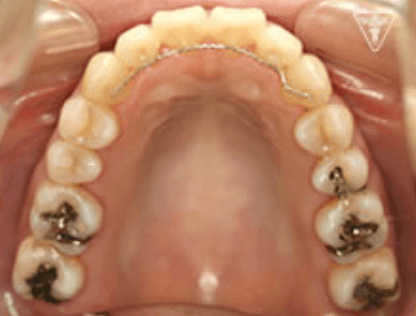

保定装置の装着

長期安定と後もどり防止のために、保定装置を装着します。

長谷川 信先生考案のフロッシュ装置(ゴムメタル使用)を夜間装置します。